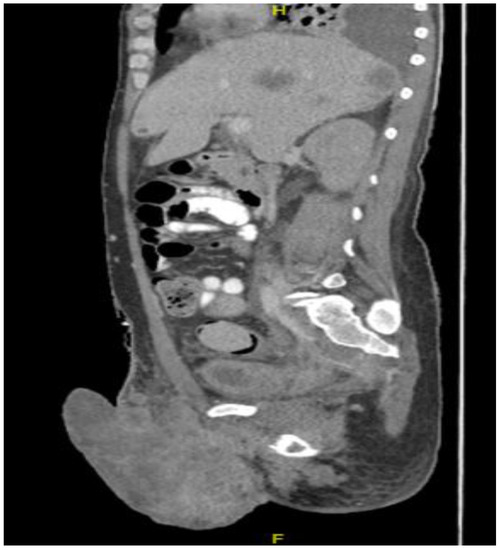

CT in the sagittal view, abdominal window, showing scrotal mass extending to erect penis.

Figure 9.

Despite palliative chemotherapy and palliative radiation, the patient’s clinical status continued to deteriorate. He developed worsening lethargy, poor intake, renal failure, and open penile and scrotal sores with purulent drainage, indicative of a superimposed infection, and he was re-admitted for further management. Imaging showed the significant further progression of metastatic disease (Figure 7, Figure 8 and Figure 9), especially in the pelvis, with new bilateral hydroureteronephrosis and evidence of ileus. He was deemed to no longer be a candidate for further radiation or systemic therapy because of his declining clinical condition. The urology staff again recommended against the resection of the scrotum and penis. He elected to pursue comfort measures only and died in hospital.